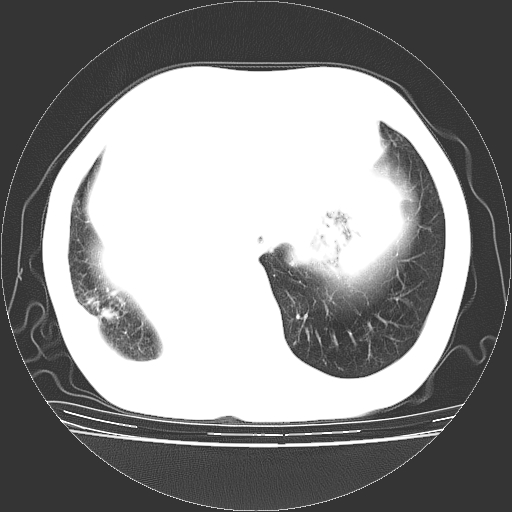

女,70岁,咳嗽、咳痰一个月,低热一周。

1.左上肺结核,部分纤维化。右肺中下叶部分肺不张,内见液化、坏死及点状钙化,右中下叶支气管壁增厚、管腔狭窄,见多个点状钙化,结合临床考虑支气管内膜结核,建议痰检查抗酸杆菌并参考血沉。两肺多个小圆点状高密度灶,境界模糊,多考虑结核肺内播散。但本人年龄较大首先应支气管镜检以除外右肺癌。

2.胸主动脉夹层。